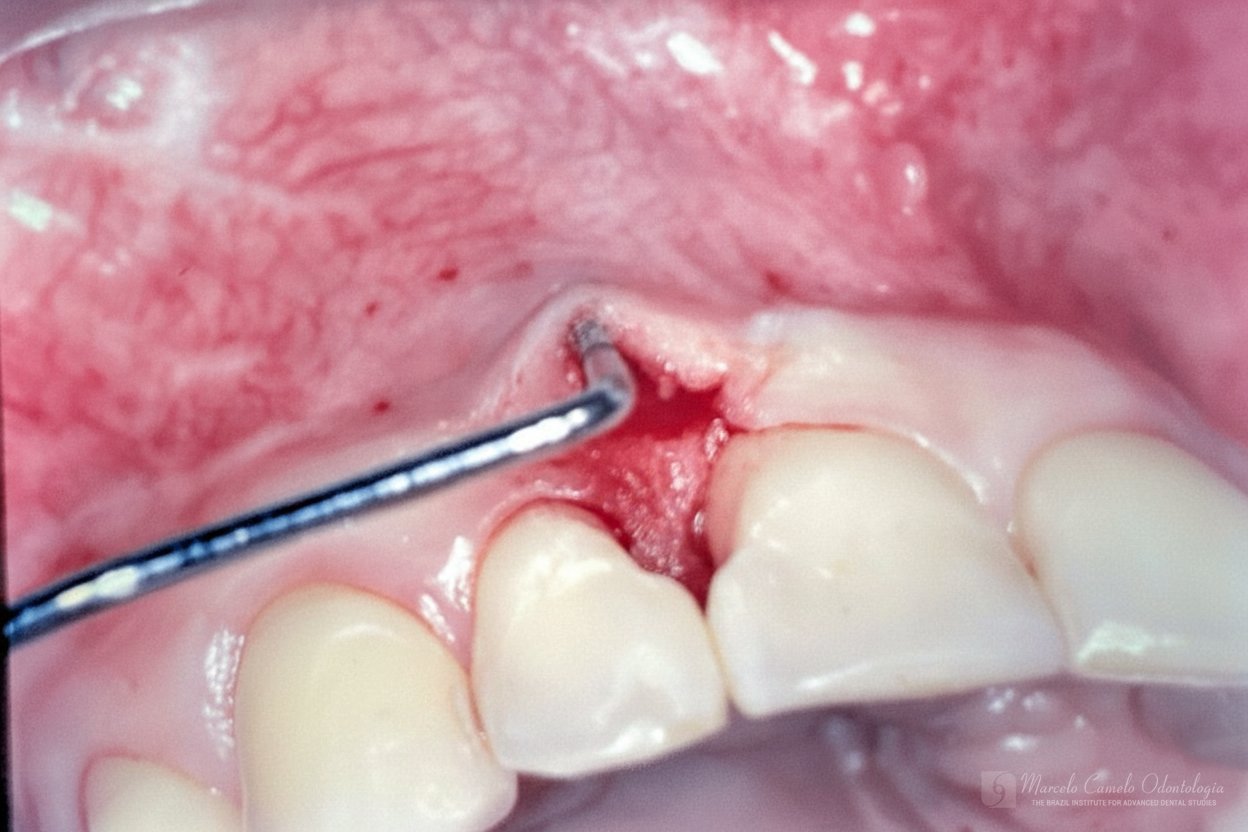

Para casos com boa qualidade de mucosa queratinizada, um envelope vestibular recebe a porção desepitelizada do enxerto pediculado.